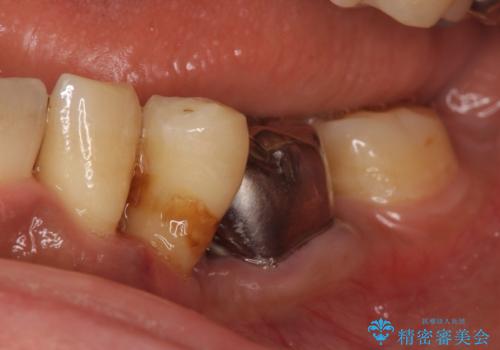

インプラント 左下奥歯の咬み合わせの改善

- 左下の歯並びが悪く、左側で物が咬みにくいので診て欲しいといらっしゃった方の症例です。

歯列矯正は御希望されなかったため左下4、5番目の歯を抜歯し、インプラントによる欠損補綴を行いました。

左下6も再根管治療後、オールセラミッククラウンによる補綴を行いました。